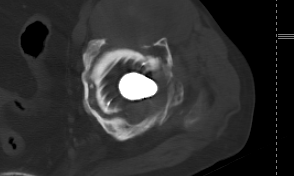

对比图像清晰显示:3月11日常规平扫图像中,金属伪影严重,结构显示不清;而3月12日采用MAR技术扫描后,无论是横断面还是冠状位重建图像,金属伪影均基本消除,解剖结构清晰可见,为临床精准评估和假体设计提供了可靠依据。

注:以下图片展示了常规平扫与MAR技术扫描的对比效果,清晰呈现金属伪影消除技术的临床价值。

MAR技术扫描(金属伪影基本消除)